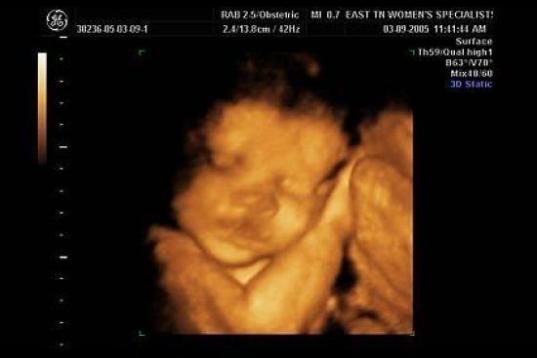

En esta galería puedes ver en fotos como es el desarrollo de un feto de semana en semana:

Desarrollo del feto, en fotos